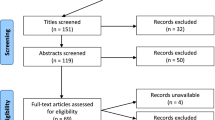

Extensive literature review was conducted to gather insights into the role of AI in skull base surgery. Key aspects such as diagnosis, image analysis, surgical planning, navigation, predictive analytics, clinical decision-making, postoperative care, rehabilitation, and virtual simulations were explored. Studies were sourced from PubMed using keyword search strategy for relevant headings, sub-headings and cross-referencing.